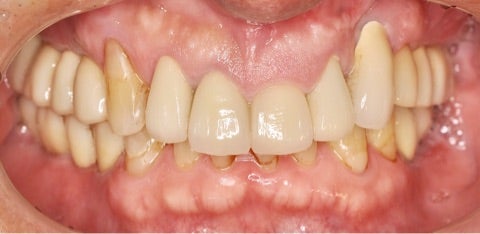

before/after

歯の動揺がなくなったことはもちろん、歯と歯茎の黒い境目や、形態不良による審美障害も改善されています。ご本人には自分の歯が残せたこと、見た目も綺麗になったことでとても喜んで頂けました。